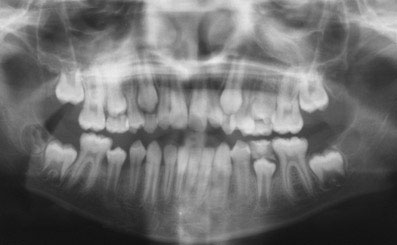

DIAGNOSTIC

Ce jeune patient présentait un schéma de classe I squelettique normodivergent (Fig. 1, 2, 3). Sur le plan occlusal, il présentait une classe 2 dentaire bilatérale, une biproalvéolie incisive sévère, une béance antérieure, ainsi qu’un articulé inversé entre 26 et 36. Les 12 et 22 étaient de taille réduite (Fig. 4, 5, 6).

Sur le plan fonctionnel, nous avons noté une succion du pouce nocturne, et une déglutition de type infantile avec interposition linguale.

Enfin, son profil était convexe avec une projection des tissus mous vers l’avant (Fig. 7, 8).